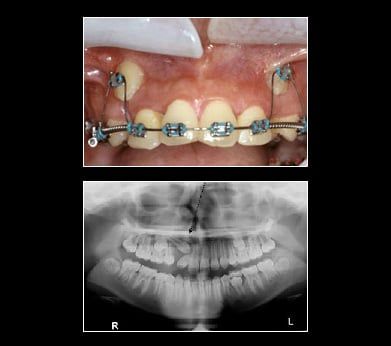

Impacted Canine

Canine teeth are also commonly referred to as cusped or "eye teeth" since the teeth align under your eyes. You should have two canines in both your upper and lower jaw. They are the strongest teeth you have, used for tearing into your most meaty meals. Because of this need for strength, your canines have the longest roots of all your teeth. They are an essential part of your bite and balanced smile for two main reasons:

- Your Bite

Due to their length, the canines guide your other teeth together when chewing and biting. Canines are essential for maintaining a proper bite. - Your Appearance

Without canines, large gaps appear in your smile. This can lead to your other front teeth becoming twisted or crooked.

Your canine teeth are generally some of the last teeth to erupt. Occasionally they do not erupt. The two most common reasons are:

- Overcrowding in your mouth

Extra teeth or a small jaw can cause the space where your canines are supposed to come in to be very small, resulting in impaction, or failure to erupt. - Abnormal growths

Tissue may have developed in your jaw that prevented your canines from reaching the surface.

The fact that teeth don't always come in like they're supposed to highlights the need for regular dental visits when young teeth are developing. If you suspect your child has impacted canines, don't hesitate to make an appointment with Pinole Periodontics & Dental Implants. With regular dental visits, x-rays and examinations, the problem of impacted canines can be found out early when treatment is easier. If you are an adult and your canines have not erupted Pinole Periodontics & Dental Implants can help. Set an appointment today for an x-ray and consultation. Your smile is up there waiting for you.

Treatment for Impacted Canines

After assessing your situation, Pinole Periodontics & Dental Implants will devise a plan to make room for your canines. With a typical oral surgery and the assistance of an orthodontist your canine will find their way into their proper place over time.